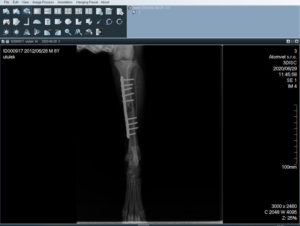

Crash – VM

30.6.2020

6292

Crash

kříženec

pes

6 roků

15 KG

Nález / v útulku od:

Trnávka Lipník nad Bečvou/ 28.6.2020

nalezen sražený autem, tříštivá zlomenina zadní končetiny